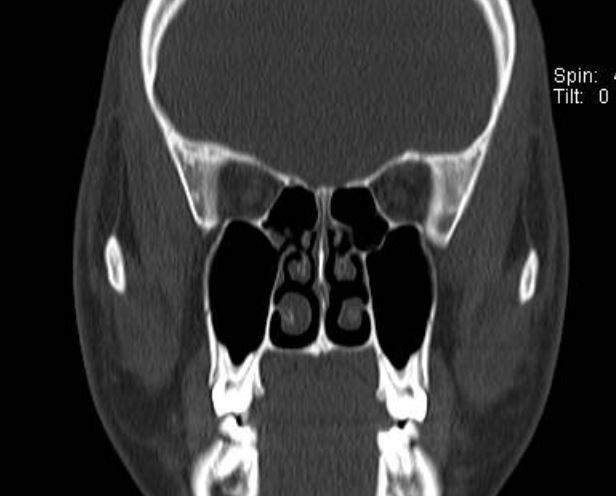

最近來自廣東佛山順德的小何,15歲,鼻塞1年多了,非常的影響學習和睡眠。在當?shù)蒯t(yī)院吃了不少的藥物,效果比較差。這次放假來找耳鼻喉鄭立崗醫(yī)生要去能徹底的解決自己的鼻塞問題,要不然影響學習時的注意力。做了鼻內鏡和鼻竇CT檢查后發(fā)現(xiàn)主要的問題是下鼻甲肥大,堵塞了鼻腔。這種情況如果藥物治療效果不好,通過鼻內鏡微創(chuàng)手術是可以解決的。由于要中考,就及時入院了。這次安排的是全麻鼻內鏡下下鼻甲射頻消融術。插管全麻后就開始了手術,在鼻內鏡下用射頻針消融雙側的下鼻甲,這樣下鼻甲就可以明顯的縮小,而且不會明顯的影響下鼻甲的功能。整個的手術用時約30分鐘,非常的順利。術后查房患者無明顯的不適,無手術相關的并發(fā)癥。對于鼻塞,如果您還有什么問題,歡迎留言和耳鼻喉鄭立崗醫(yī)生進一步交流。